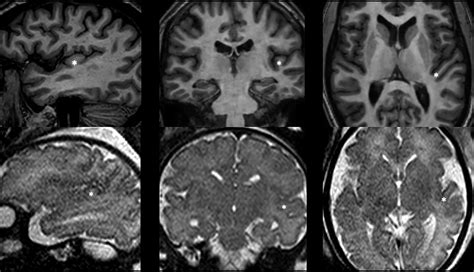

• Neuroimaging Studies: Using techniques such as functional magnetic resonance imaging (fMRI) and positron emission tomography (PET) to map the activity and connectivity of the Transverse Temporal Gyri.

A 55-year-old patient presented with difficulty recognizing familiar sounds, including speech, despite having normal hearing. Neuroimaging revealed damage to the Transverse Temporal Gyri due to a stroke. The patient underwent intensive speech therapy and auditory training, which helped improve their ability to recognize and interpret sounds.

A 30-year-old musician reported a lifelong inability to recognize or reproduce musical tones. Neuroimaging studies showed abnormalities in the Transverse Temporal Gyri. The patient was diagnosed with congenital amusia and received specialized music therapy to enhance their musical abilities.

A 45-year-old individual complained of persistent ringing in the ears, which was diagnosed as tinnitus. Neuroimaging and electrophysiological studies indicated hyperactivity in the Transverse Temporal Gyri. The patient was treated with a combination of sound therapy and cognitive-behavioral therapy, which helped reduce the severity of the tinnitus.